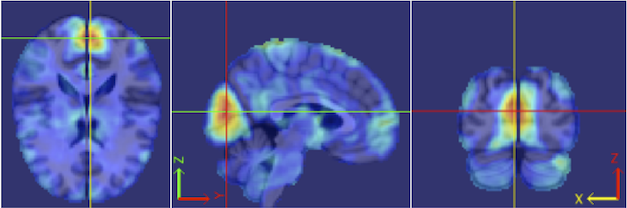

Our procedure is as follows. Each fMRI scan was separated into left and right hemispheres. Thus, each hemisphere contained voxels. Similar to standard group ICA (Calhoun et al., 2001b), a dimension reduction using PCA was applied to each hemisphere of each subject. 15 PCs are obtained for each hemisphere. A group data matrix was generated by concatenating the reduced data of both hemispheres of the 20 subjects in the temporal domain. Thus, the aggregated matrix has dimension , where , , and . Our algorithm of homotopic group ICA is then applied on this matrix. Fifteen estimated independent components are postulated by H-gICA. As shown in Figure 12, out of the 15 components, several brain networks were found including: the visual network 12, the default mode network 12, the auditory network 12, and the motor network 12. Compared with the ICs obtained from ordinary gICA, shown in 12, 12, 12 and 12, H-gICA improves the estimation of all of these sources by yielding substantially more clearly delineated networks.